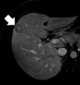

Liver lesion with central scar